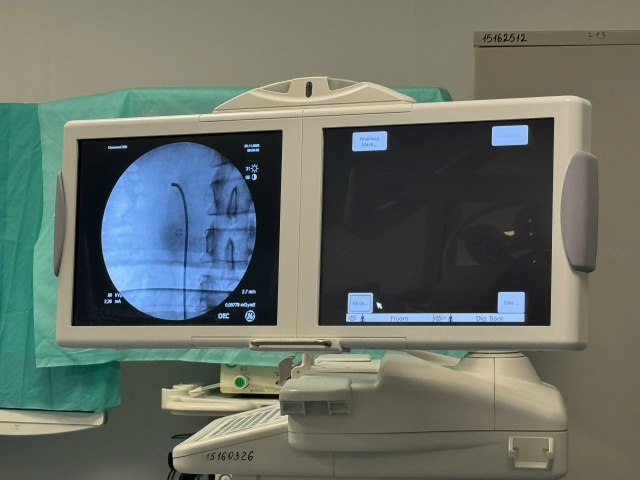

Источник: progorodsamara.ru

Литотрипсия (lithos «камень» и tripsis «дробление») – это современный способ удаления камней с помощью дробления (ударным волнами, лазером, ультразвуком), как раз он и используется в клинике «Реавиз».

– Мы используем разные методы литотрипсии, – рассказывает врач-уролог. – И на каждый вид камня есть свой метод лечения.

– В нашей клинике для лечения МКБ мы полностью отошли от открытой хирургии с большими разрезами и от ДУВЛ – так как его принцип действия основан на сильных ударных волнах, достаточно травматичных. Сейчас мы используем минимально инвазивные методы литотрипсии – RIRS и mini-PCNL.

В таком случае делается небольшой прокол в области поясницы и через этот прокол лазером убирается конкремент, – описывает процедуру доктор. – Если он маленький, используется специальный тонкий инструмент: врач заходит им через естественные пути, доходит до почки и лазером изнутри дробит его в пыль. Осколки достают – внутри не остается ничего.

Готовиться к операции следует тщательно, проходя полное обследование, в том числе, КТ с контрастным веществом. Это повышает точность и безопасность процедуры. Хирурги-урологи планируют операцию виртуально, а потом воплощают план в жизнь. Ни локализация, ни объем камней не влияют на эффективность операции.

– Мы беремся за любые камни и сочетаем разные методы, – объясняет Михаил Юрьевич. – Я могу зайти через прокол в почку, раздробить один камень, а затем зайти снизу, и раздробить другой. Можно сочетать разные методы в одной операции.

В большой хирургии не все доступно человеческому глазу, а благодаря этим методикам мы все видим на кончике инструмента. К нам направляют пациентов из области, районов, в том числе по ОМС.